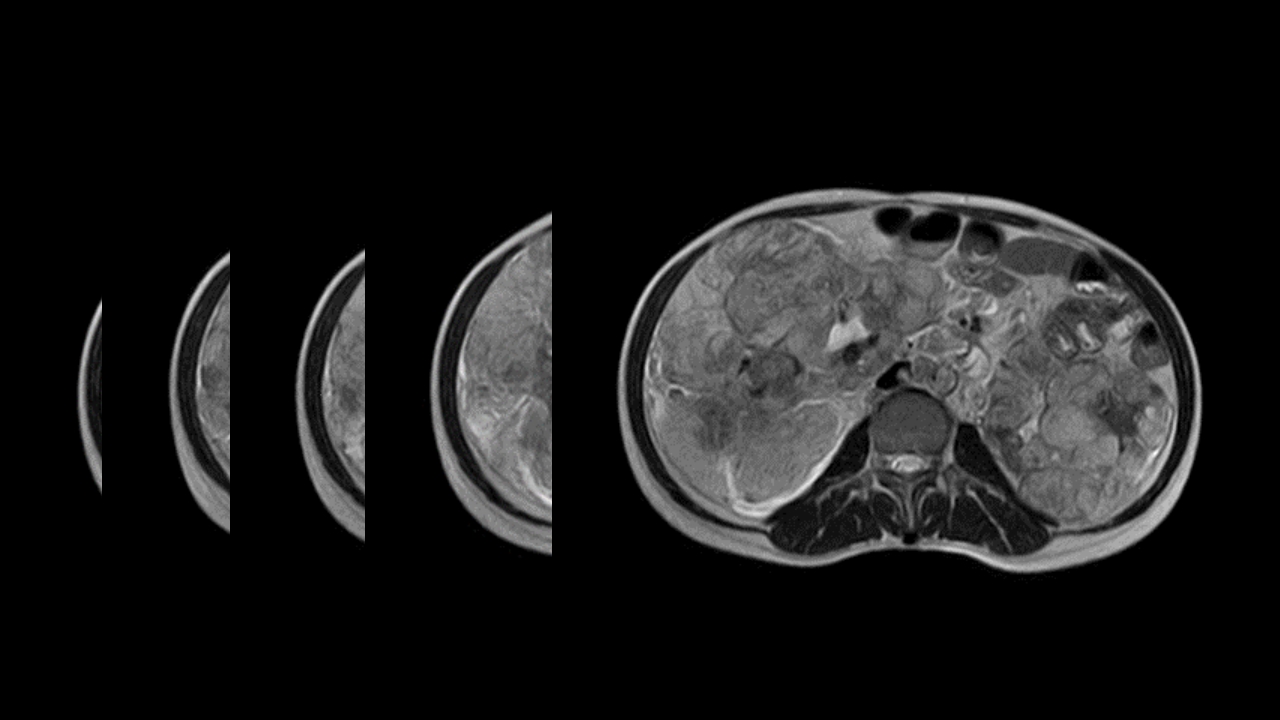

肺淋巴管肌瘤病合并双侧巨大肾血管平滑肌脂肪瘤(X线、CT、MR)